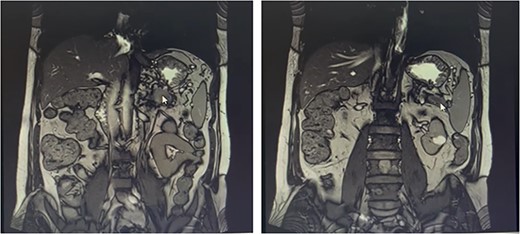

Our patient is a 55-year-old man with a history of rectal adenocarcinoma cancer in the last 2 years. At that time, he presented with flank pain and kidney stones. After examination and diagnostic tests, he was diagnosed with colon cancer that a 12 cm mass was reported and then colectomy surgery was performed. Then six sessions of radiotherapy were considered for him. In the new regression, 2 years after the colectomy surgery, during the examination phase, due to the exacerbation of pain, a computed tomogaphy (CT) scan (Figs 1 and 2) and endoscopy were requested for the patient, in which pancreatic cancer was observed. After that, the patient was placed under endoscopic ultrasound (EUS), which is reported. There was one 35 × 29 mm hypoechoic and round lesion with ill-defined border in pancreatic tail with no involvement of pancreatic duct or splenic vessels in favor of metastasis. EUS fine-needle biopsy with needle 22G was performed. Then the patient underwent a biopsy and the final confirmation was made.

Metastatic masses can be seen in the pancreatic tissue on the CT-Scan (transverse/axial view)

Metastatic masses can be seen in the pancreatic tissue on the CT-Scan (coronal view)